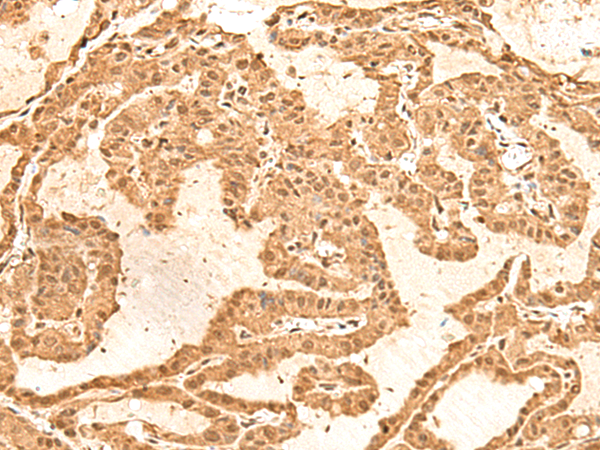

IHC positive control:

Human esophagus cancer and Human thyroid cancer

IHC Recommend dilution:

50-300